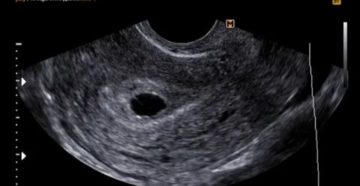

Необходимость хирургического вмешательства при анэмбрионии Проблемы с нормальным вынашиванием и последующим деторождением могут быть связаны…